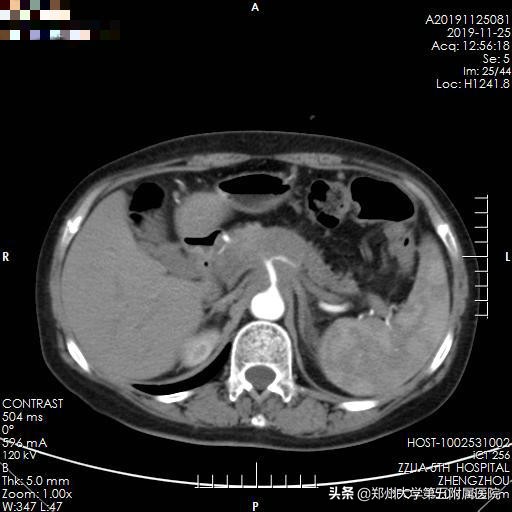

▲ 图 1 患者术前增强CT检查

2019年11月29日下午3点,手术如期进行,在手术室胡强夫主任团队,超声诊断科杨青主任团队缜密的配合下,李晓勇主任团队联合台湾大学附属医院黄凯文教授,通过术前增强CT与术中实时彩超融合引导,精确定位肿瘤位置,精准穿刺布针,纳米刀消融时间约15分钟,术中彩超提示肿瘤消融彻底,效果满意,且周围重要血管流动通畅,未见出血、胃肠道的损伤。